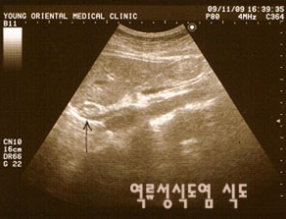

<강남영한의원 역류성식도염 환자>

역류성 식도 질환은 위산이 식도 내로 역류하면서 증상을 나타내는 것을 가리키는 말이다. 이 중에서도 내시경 검사로 위액의 식도 내 역류에 의해 식도점막에 궤양이나 미란성 염증이 생긴 것이 확인되면 역류성 식도염이라고 한다.

<사진출처> 강남 영한의원 최승영원장